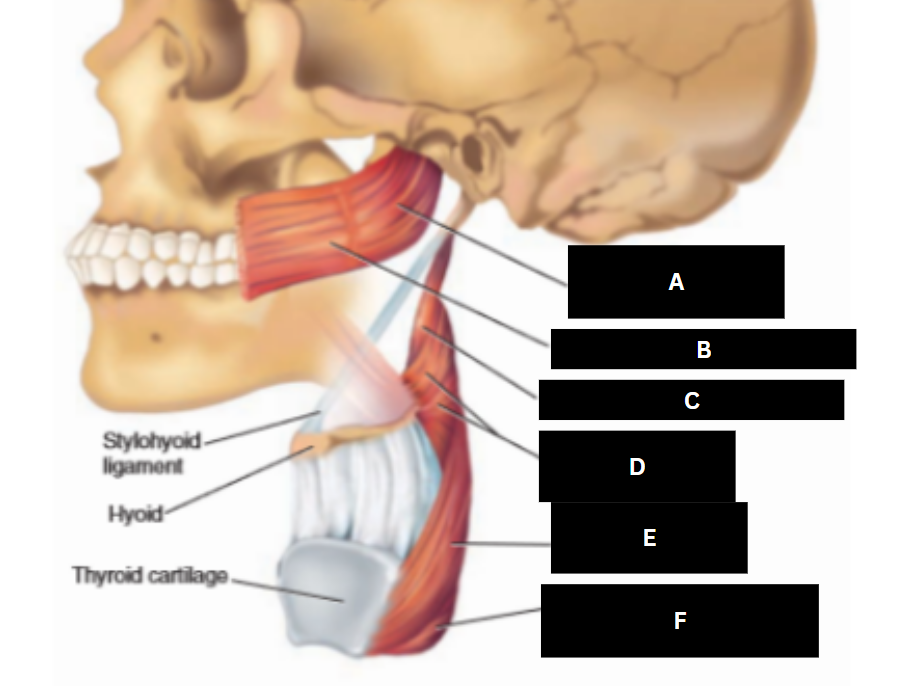

Stylopharyngeus

A

Styloglossus

B

Stylohyoid

C

Cricopharyngeus

D

Superior pharyngeal constrictor

E

Middle pharyngeal constrictor

F

Pharyngeal raphe

G

Inferior pharyngeal constrictor

H